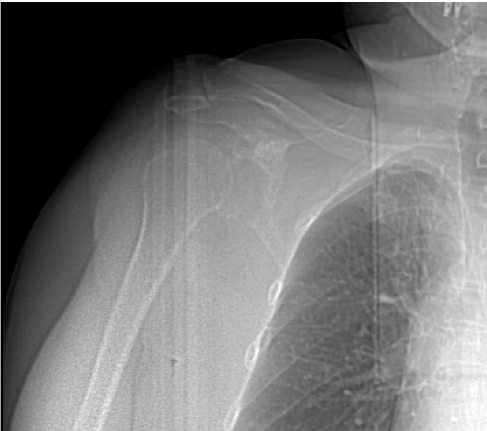

Pre-op

- 60 year-old patient

- Sarcoma of right scapula